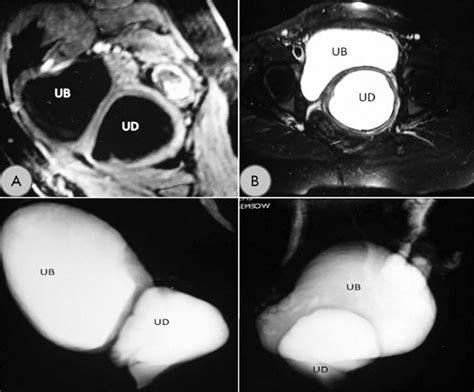

MRI (Magnetic Resonance Imaging) The gold standard for visualizing the size and location of the diverticulum.

Voiding Cystourethrogram (VCUG) Uses contrast dye to see if the pouch fills during urination.